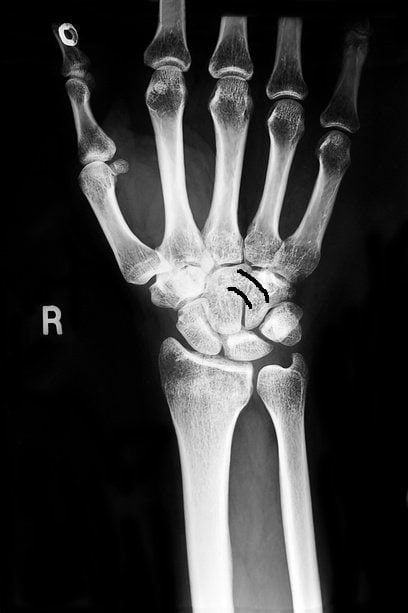

Травмы

Они могут быть диагностированы самим пострадавшим: боли весьма яркие, иногда доходящие до уровня нестерпимых. Что именно травмировано в лучезапястном суставе, определить может только врач, поскольку может сместиться головка кости, разорваться сухожилие или сломаться сам луч. Последняя травма считается самой сложной.

При травматическом поражении лучезапястного сустава наблюдается острая боль, быстрое отекание мягких тканей, ограничение в подвижности кисти или полное отсутствие возможности ею шевелить. Иногда имеет место деформация предплечья.